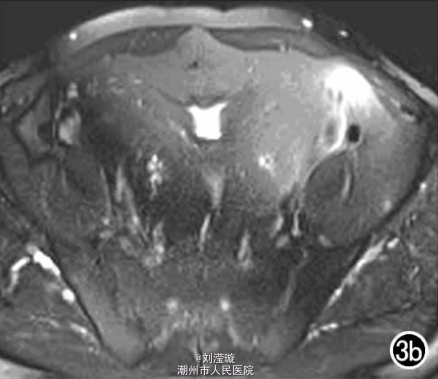

腹部B超示双肾增大,双肾慢性肾病声像;双肾中度积液伴双输尿管上段扩张。 IVPshi双侧输尿管中或下段梗阻。 膀胱造影:经尿道置管后,注射对比剂充盈膀胱,膀胱下半部先充盈,继续灌注对比剂后见膀胱完全显影,膀胱形态异常,呈“倒葫芦状”(图1)。 CT增强扫描行延迟期 MPR重组,见双侧肾盂、肾盏扩张积液;双侧输尿管纡曲、扩张,下端呈鸟嘴样变窄;膀胱变形、体积减小(图2); MRI平扫示双侧肾盂、肾盏扩张积液,双侧输尿管扩张并下端鸟嘴样变窄,盆腔内多量脂肪沉积,分布于膀胱、直肠周围,T1WI、T2WI呈明显高信号,T2WI抑脂像呈稍高信号,膀胱受压变形、体积减小(图3a~c); MRU示双侧肾盂肾盏扩张、积液,双侧输尿管显著纡曲、扩张,下端鸟嘴样变窄,管壁光整,膀胱变形、体积较小、位置抬高(图3d)。

综合影像资料,该例符合盆腔脂肪增多症典型改变。 于全麻下行剖腹探查术,适当清除双侧输尿管周围、膀胱周围及腹膜后脂肪,离断双侧输尿管下段后行输尿管膀胱再植术。取活检病理结果为纤维脂肪组织。